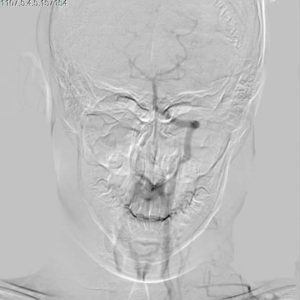

- وضع جهازي “قثطرة قلبية تصوير ثلاثي الأبعاد” و”طبقي محوري متعدد الشرائح” بالخدمة في الهيئة العامة لمشفى الشهيد باسل الأسد لأمراض وجراحة القلب بدمشق.